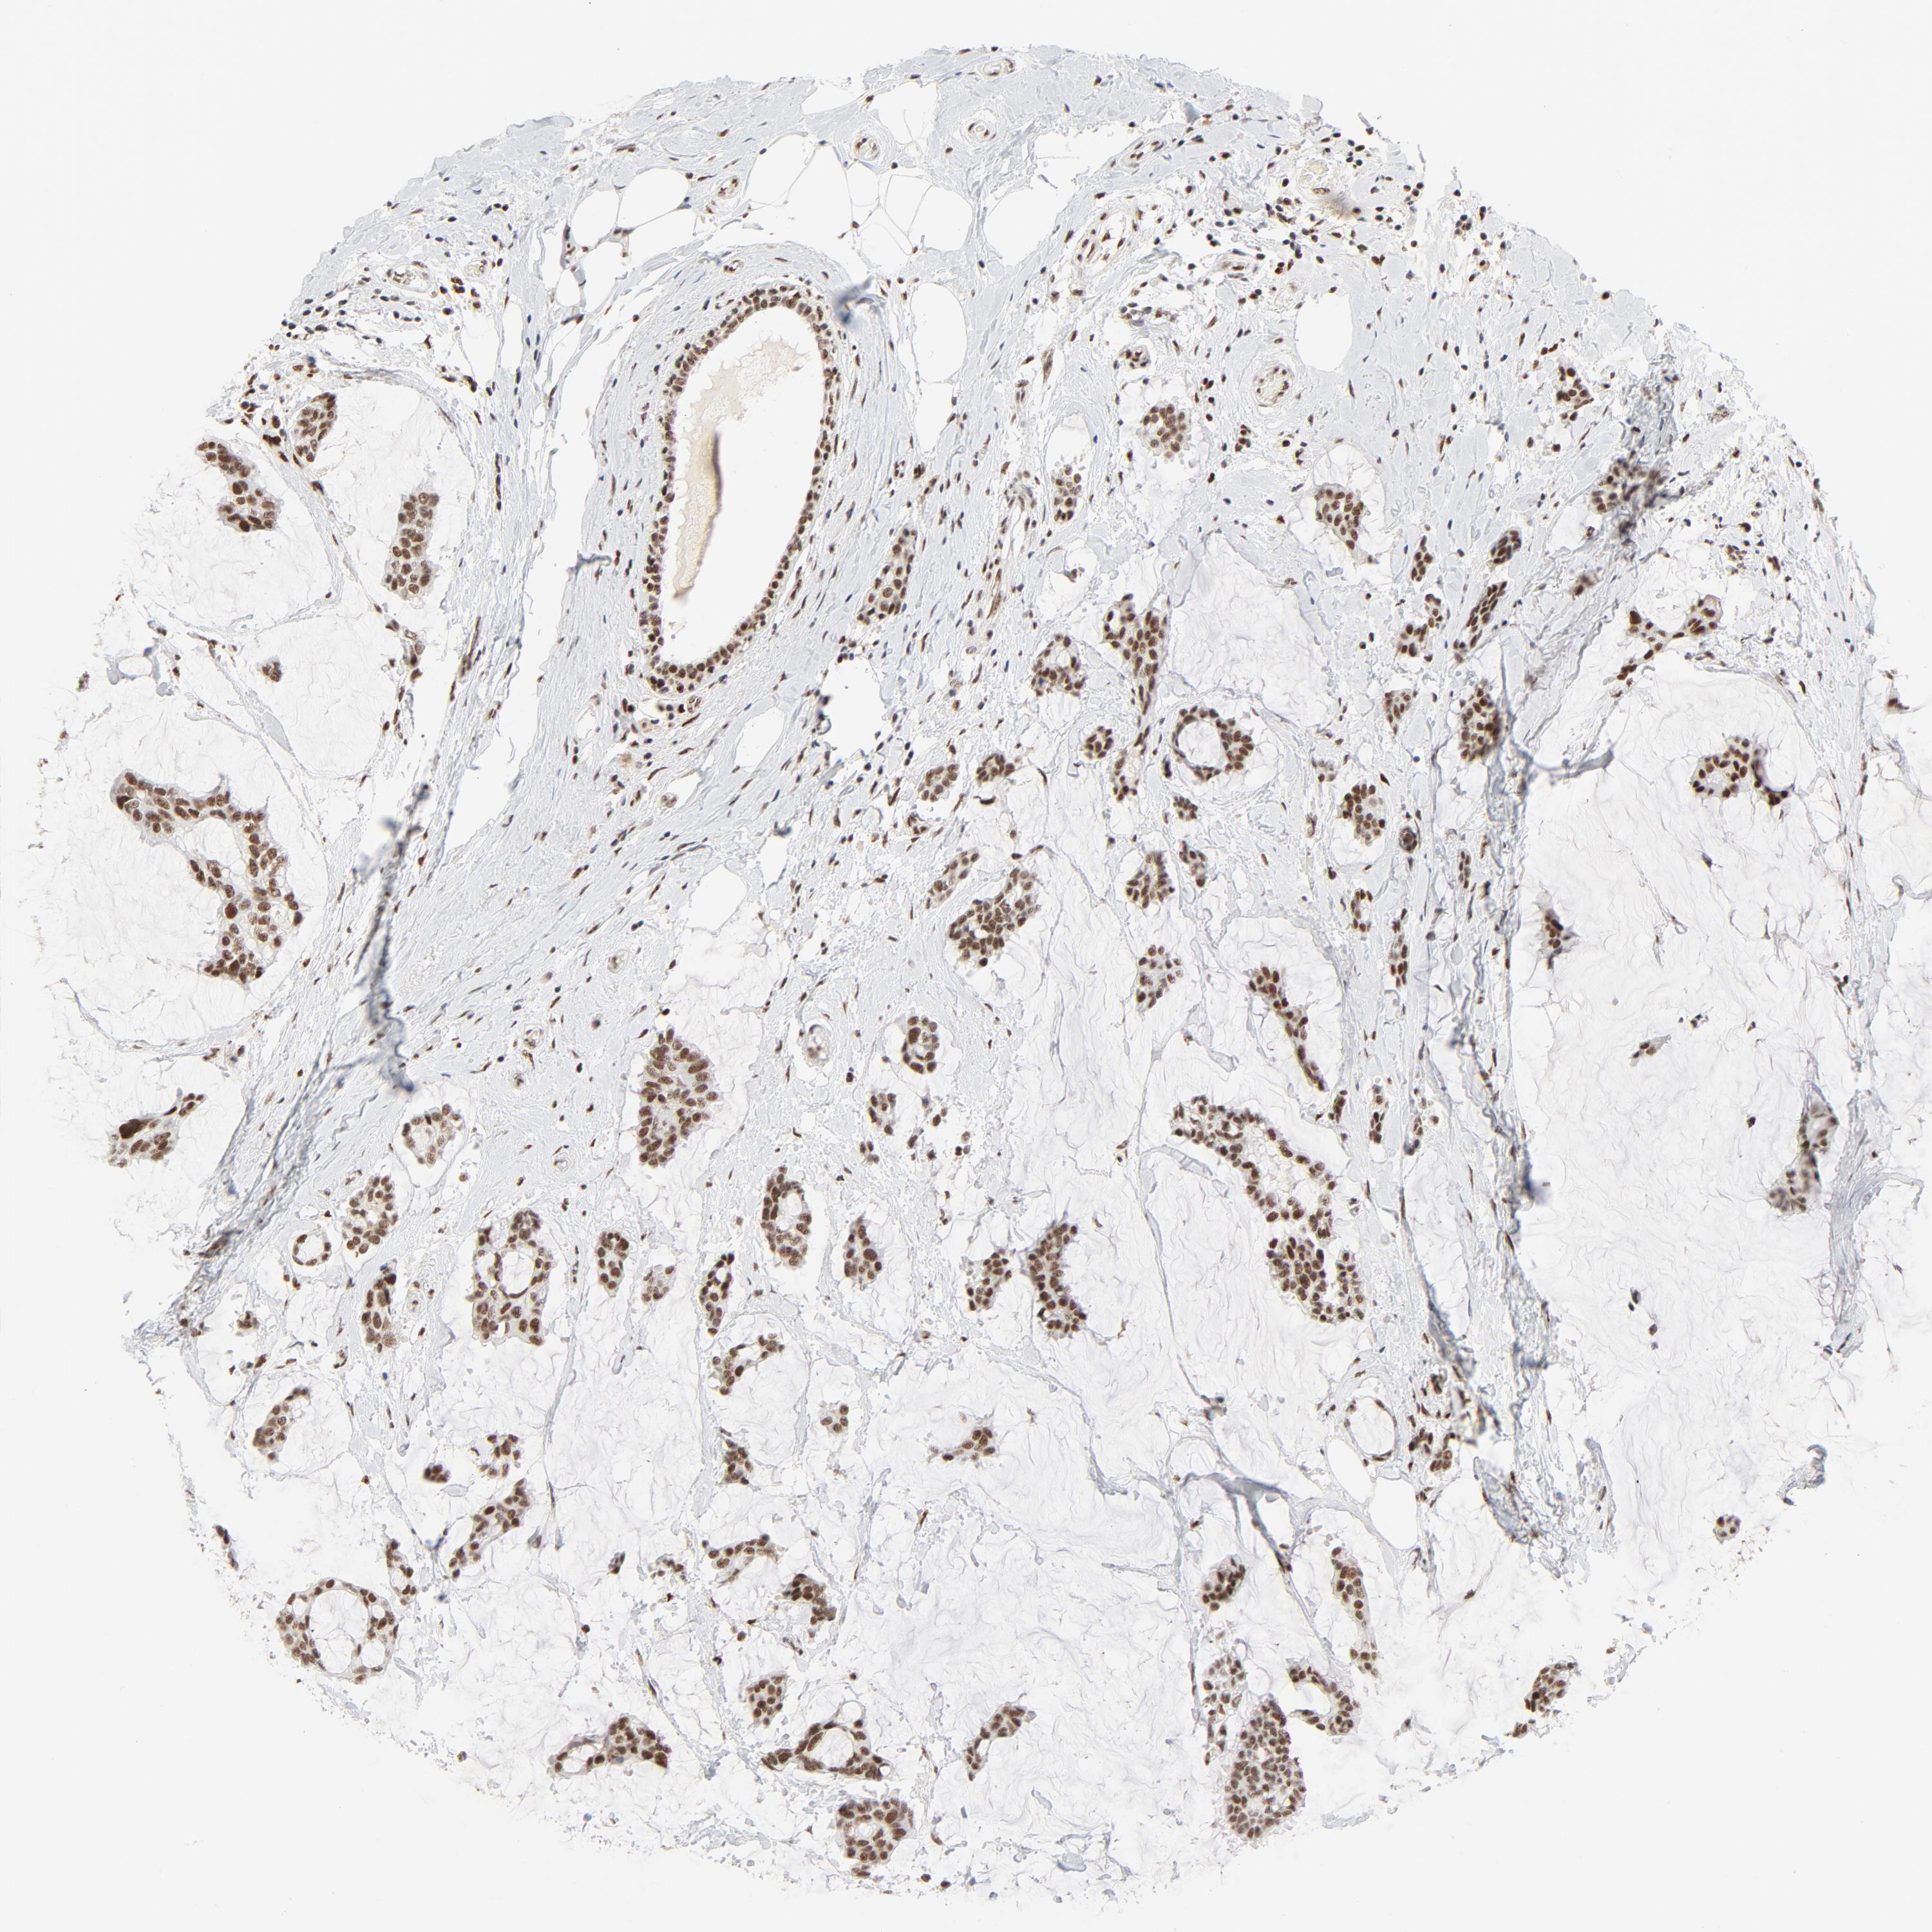

CANCER BREAST CANCER Show tissue menu

BRCA TCGA BRCA VALIDATION PROTEIN EXPRESSION